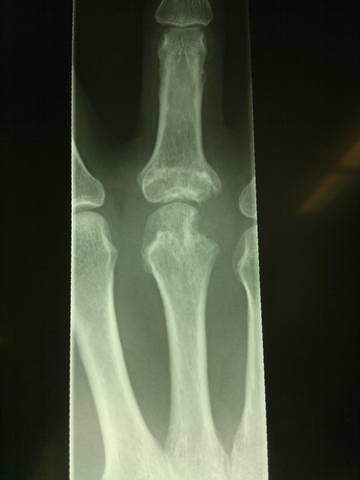

Хондросаркома головки 3 пястной кости правой кисти

Выкладываю в плане общеобразовательном, т.к. в нашей клинике мы не занимаемся лечением подобных вещей, а всего лишь выявлением.<br /><br />Около 2-х лет назад у этого 47-летнего господина появились ноющие ночные боли в области 3 пястно-фалангового сустава правой кисти, с которыми он обратился в поликлинику по месту жительства, где были сделаны первые рентгенограммы, однако пациент продолжал лечиться консервативно. Спустя 1 год симптомы заболевания не уходили и пациенту на консультации у ортопеда было предложено оперативное лечение с предварительным гистопатологическим исследованием опухолевидного образования. Исследование было проведено 2-ды и ни в одном из них не было выявлено злокачественных клеток. Операция плановая, ничего не предвещает беды, все откладывается еще на год.<br /><br />Затем пациент попадает в клинику хирургии верхней конечности, где делаются повторные рентгенограммы, на которых выявляется резорбция (остеолиз) костной ткани в области головки 3 пястной кости. Последняя увеличена в размерах, безболезненна на ощупь, кожа над ней спаяна, беспокоит незначительная боль ночью.<br /><br />

<br /><br /><br />Выполняется биопсия в 3-й раз - низкодифференцированная хондросаркома головки 3 пястной кости правой кисти. Клиническое исследование и консультация онколога - T1M0N0. Опухоль по заключению онколога не чувствительна к лучевой и низко чувствительна к химиотерапии. Рекомендована - ампутация 3-го луча. <br /><br />После чего сегодня и была выполнена эта интереснейшая операция по подробному изучению анатомии кисти и освежению в памяти навыков препарирования